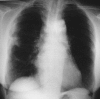

Case presentation: Here, we describe a rare case of acute fibrinous and organising pneumonia, in an otherwise healthy 65-year-old Greek woman who complained of dry cough, fever, weight loss and progressive dyspnoea. She had never been a smoker. Her clinical symptoms showed a rapid deterioration in the two weeks before admission, despite a course of oral antibiotics. After excluding infection and malignancy with routine laboratory tests and flexible bronchoscopy, high resolution computed tomography and video assisted thoracoscopic lung biopsy were performed. Diagnosis was based on radiological features typical of community organising pneumonia coupled with pathologic features characteristic of acute fibrinous and organising pneumonia. The patient was treated with corticosteroids and showed excellent clinical and radiological response three months after treatment initiation.